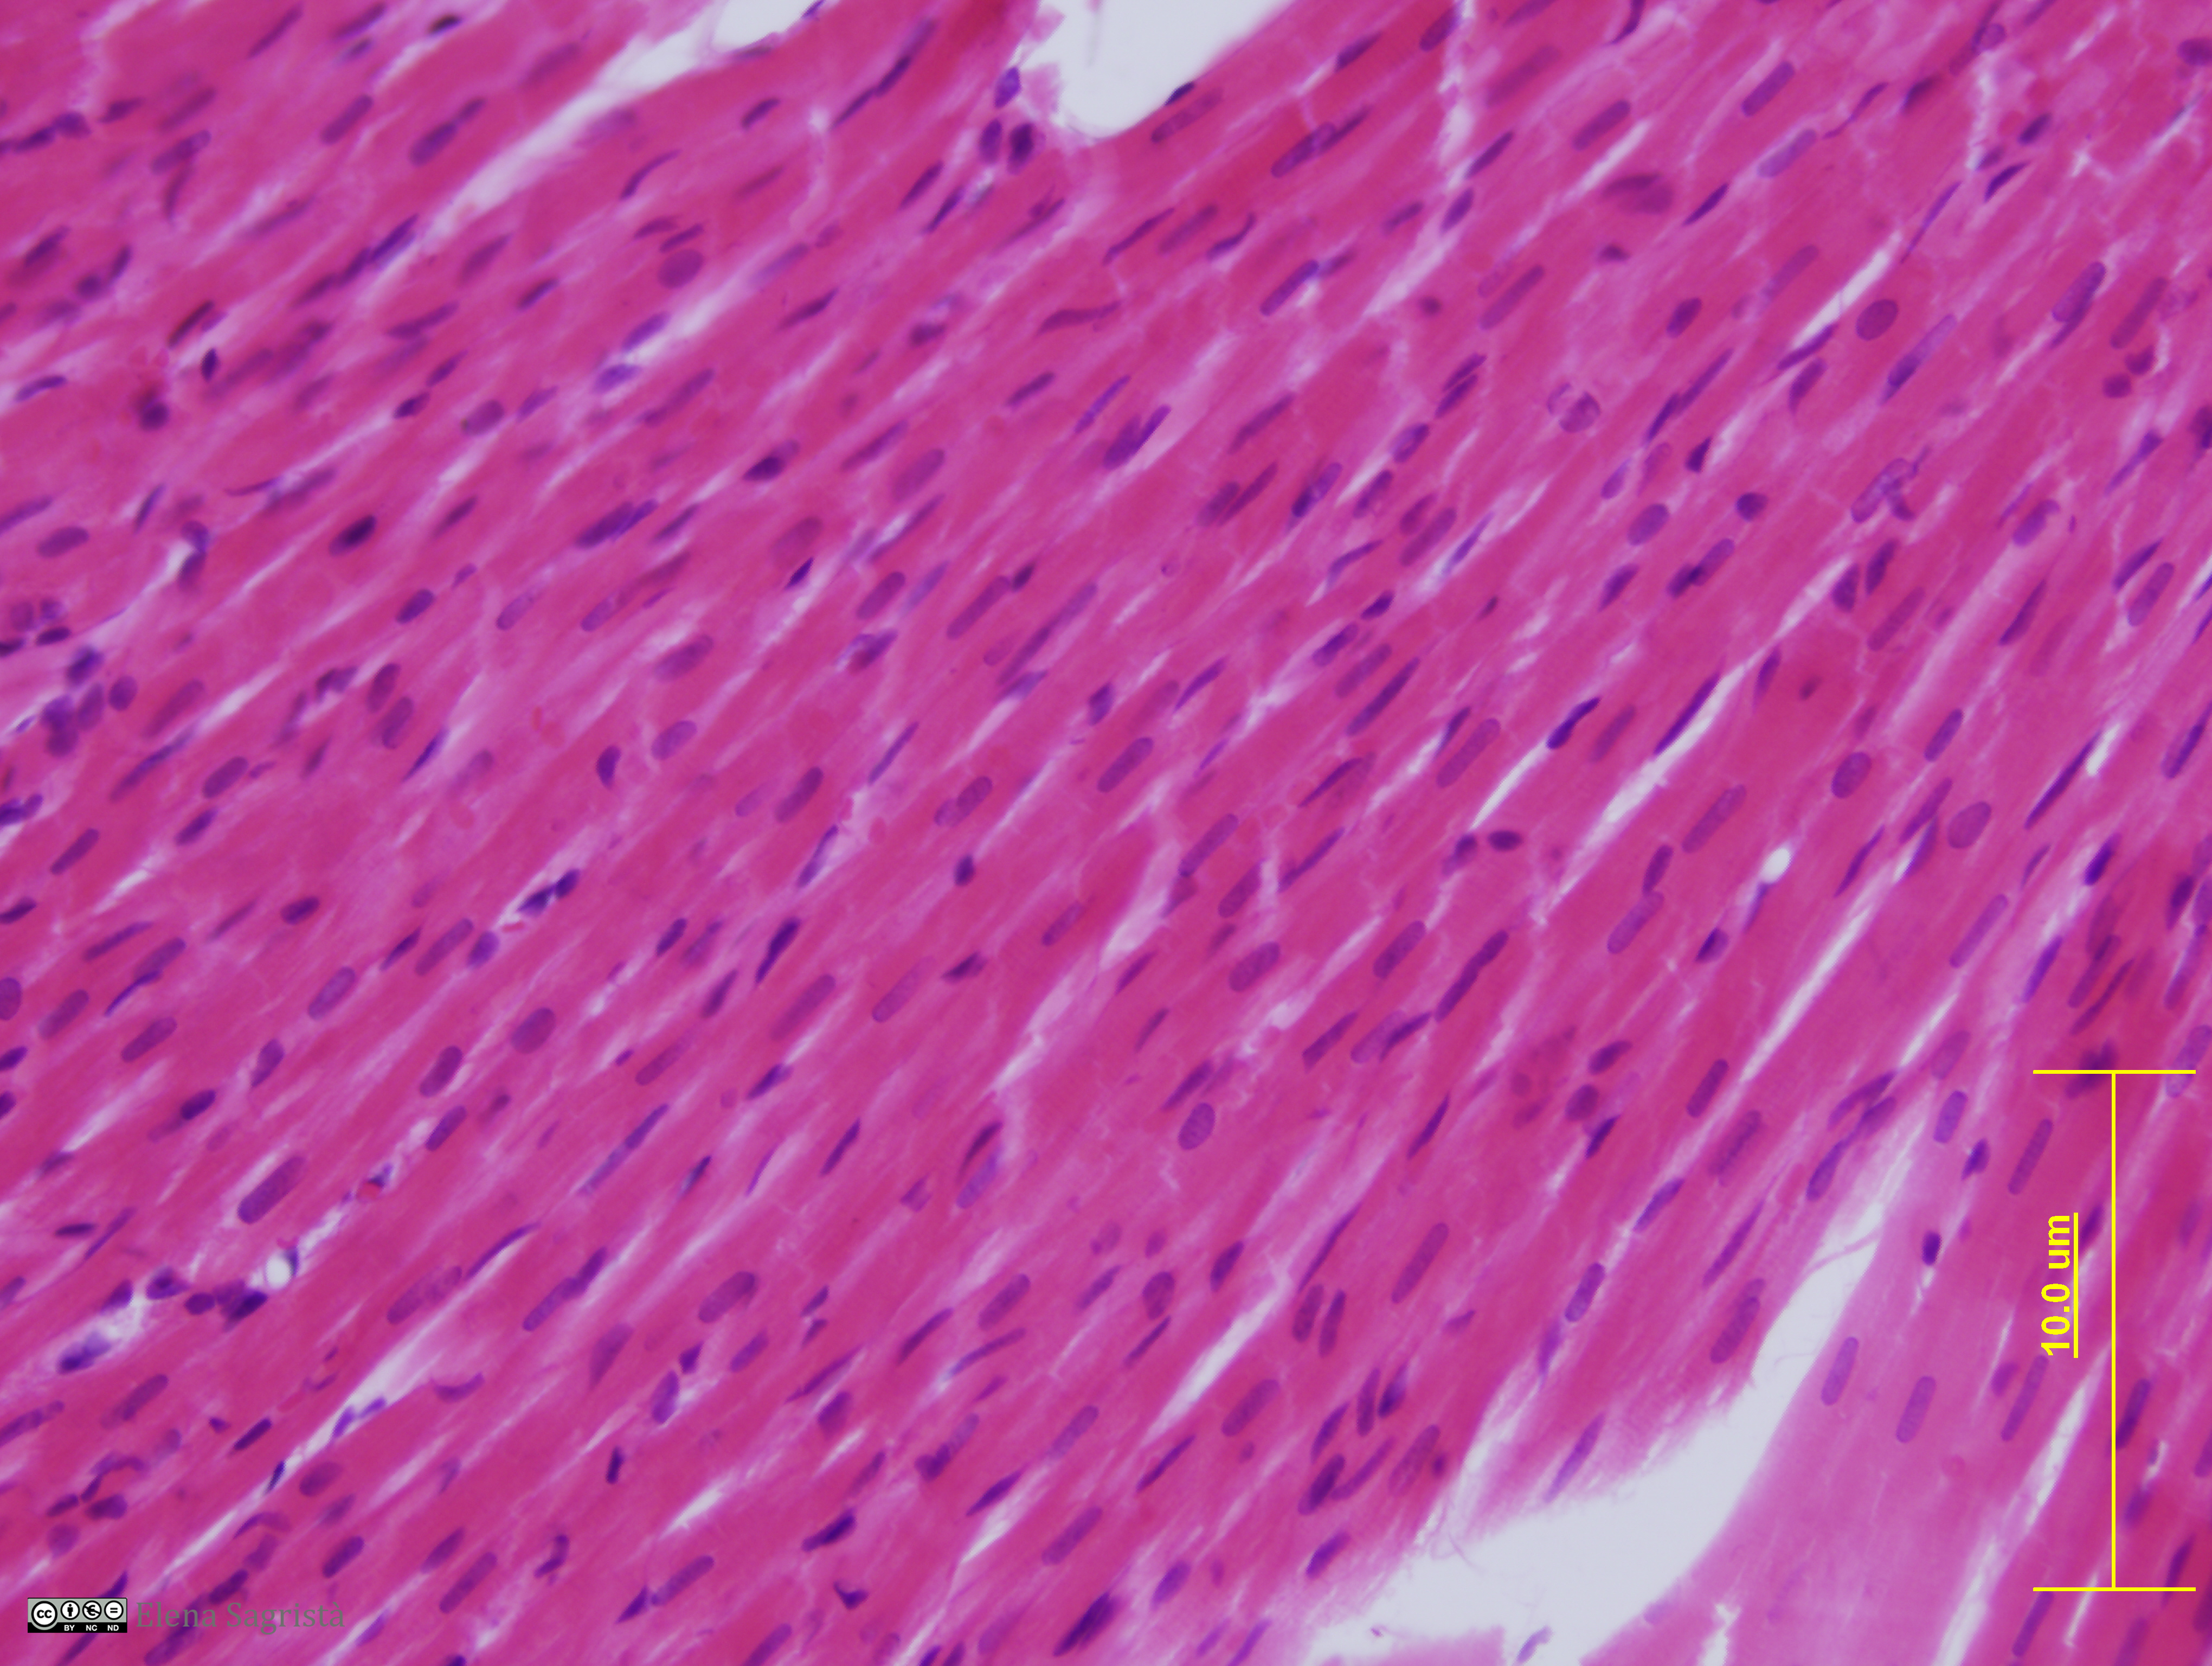

Histologia imatges: 07 Teixit muscular

Imatges de preparacions histològiques de Teixit muscular. Microscopia òptica.